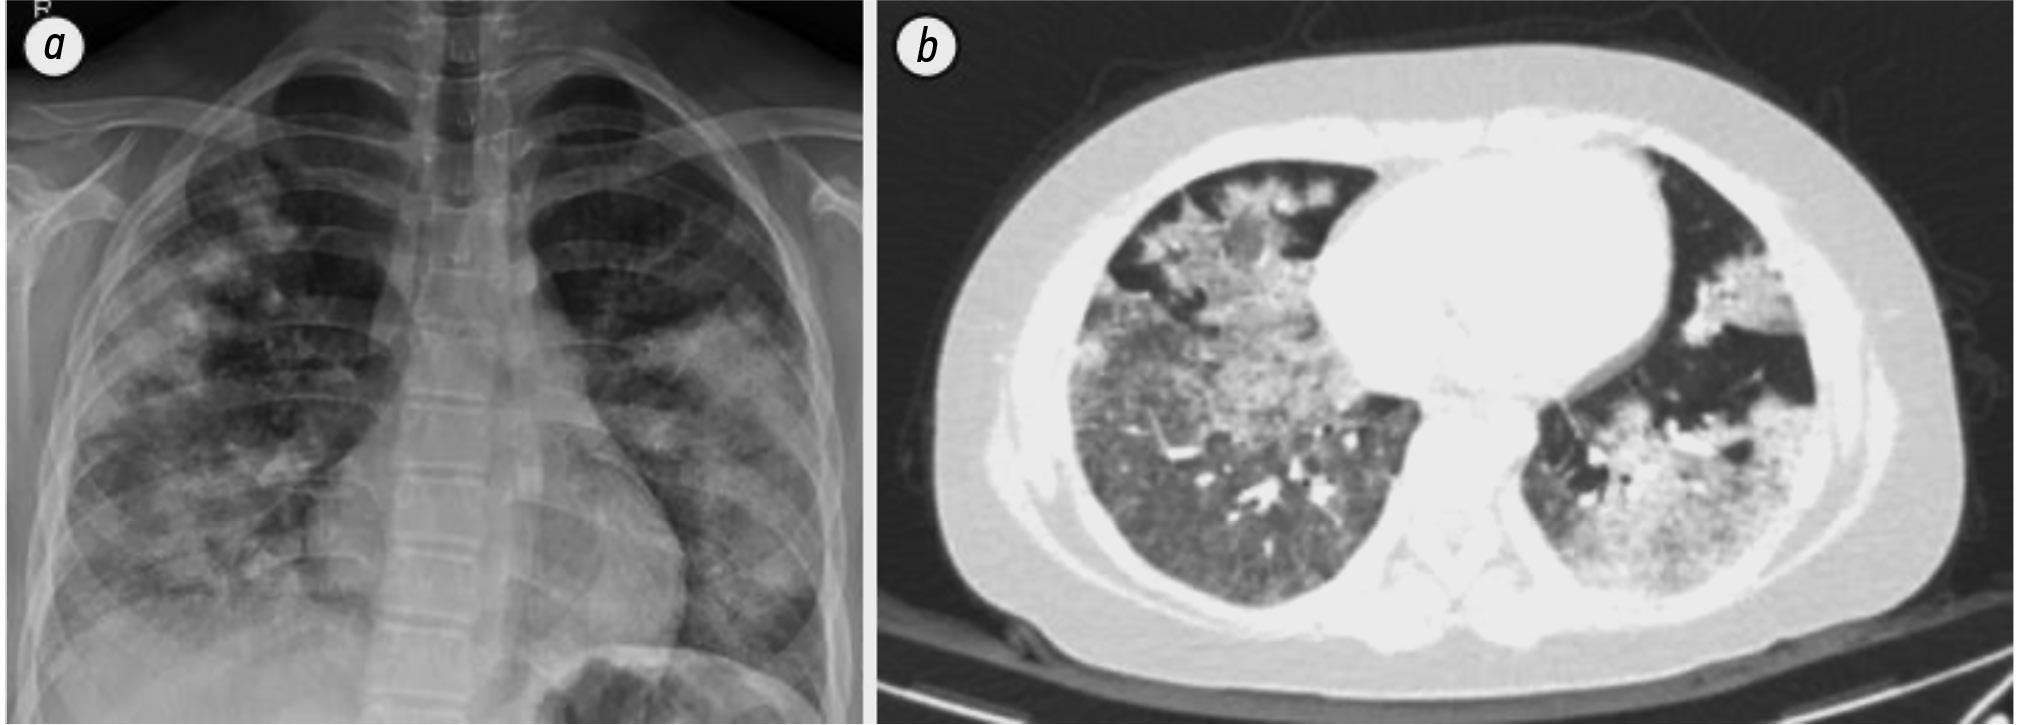

Of particular interest is a case of antineutrophil cytoplasmic antibody-associated vasculitis in a 13-year-old girl with WD [13]. The patient had been taking penicillamine for 5 years and presented to the emergency department with hemoptysis and dyspnea. Chest computed tomography revealed diffuse pulmonary hemorrhage (Fig. 3). Blood tests showed high titers of myeloperoxidase antibodies, and urinalysis revealed microscopic hematuria and proteinuria. Kidney biopsy demonstrated pauci-immune glomerulonephritis with cellular-fibrous crescents in 39% of glomeruli (Fig. 4). The patient’s condition was complicated by progressive respiratory failure, requiring respiratory support. Penicillamine was replaced with trientine. After three plasmapheresis sessions and three intravenous infusions of high-dose methylprednisolone (1 g/day), followed by cyclophosphamide (750 mg/m2), prednisolone (60 mg/day), and mycophenolate mofetil (1500 mg/day), the patient’s condition improved significantly. Respiratory failure was relieved within several days, and hematuria and proteinuria resolved 5 months after treatment initiation. Myeloperoxidase antibody titers decreased significantly within 17 months after the discontinuation of penicillamine [13].

Fig. 3. Radiography (a) and computed tomography (b) of the lungs of a 13-year-old female patient with Wilson's disease and anti-neutrophil cytoplasmic antibody-associated vasculitis: a — radiographic bilateral extensive focal consolidation; b — multifocal patchy ground-glass opacity corresponding to diffuse pulmonary hemorrhage [13]. © The Korean Academy of Medical Sciences, 2019.